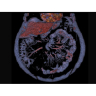

Кардиология

• Неинвазивная оценка состояния коронарных артерий.

• Диагностика атеросклероза и других сердечно-сосудистых патологий.